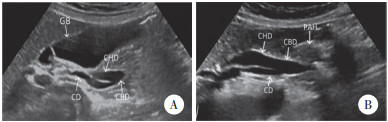

患者出院3个月后,于门诊复查超声,结果提示胆囊管内径约0.47 cm,长度约4.98 cm,肝总管内径约1.09 cm,长度约3.95 cm,胆总管内径约0.87 cm,长度约2.72 cm,胆囊管在肝外胆管下段汇入其内,综上判断为肝外胆管扩张,LICD可能性大(图 2)。结合既往MRCP检查见肝外胆管扩张,胆囊管汇入位置低,汇入点位于胆总管左侧壁(图 3),证实患者为胆囊管低位螺旋汇入。患者因自觉无明显不适,选择定期超声复查。本研究获得我院医学科学伦理委员会批准。

| A,与胆囊(GB)相连接冗长扩张的胆囊管(CD);B,胆囊管(CD)与扩张的肝总管(CHD)伴行,最终汇合成胆总管(CBD)进入胰头(PAH). 图 2 复查超声图像 |

胆囊管解剖变异的诊断主要借助影像学检查,MRCP是目前胆道解剖学检查中侵入性最小、最可靠的检查方法[8],能全面地显示胰胆管的解剖结构及连接关系,可诊断包括LICD在内的胆管解剖变异[9],有文献[10]报道MRCP诊断胆管解剖变异的准确率高达96.9%。但MRCP对胆管周围组织的定性诊断较差,且易受伪影影响,目前仍不能作为胆道系统疾病的常规检查项目。超声检查是诊断胆道疾病的首选方法,但目前对于LICD的超声诊断报道较为罕见,这可能与未扩张的胆囊管在超声检查中显示困难及超声医生对胆囊管解剖变异认识不足有关。本例患者在既往超声检查中,由于初诊超声医生对LICD认识不足,将相互伴行的胆囊管和肝总管误认为胆总管上段,将胆囊管和肝总管二者相重叠的管壁回声误认为胆总管上段腔内的条带状回声(图 1),而复查超声时发现第一肝门处2条胆管回声,右侧的胆管向上与胆囊相连接,为冗长扩张的胆囊管(图 2A),左侧胆管与肝内的左右肝管相连接,为扩张的肝总管,最终二者汇合成胆总管进入胰头(图 2B),胆囊管在肝外胆管下段汇入,因此,超声诊断为LICD。但超声检查目前很难确定胆囊管汇入点的位置,还需借助MRCP进一步明确。本例LICD患者的3D-MRCP图像可清晰显示胆囊管汇入点位于胆总管的左侧壁(图 3),属LICD的低位螺旋汇入。